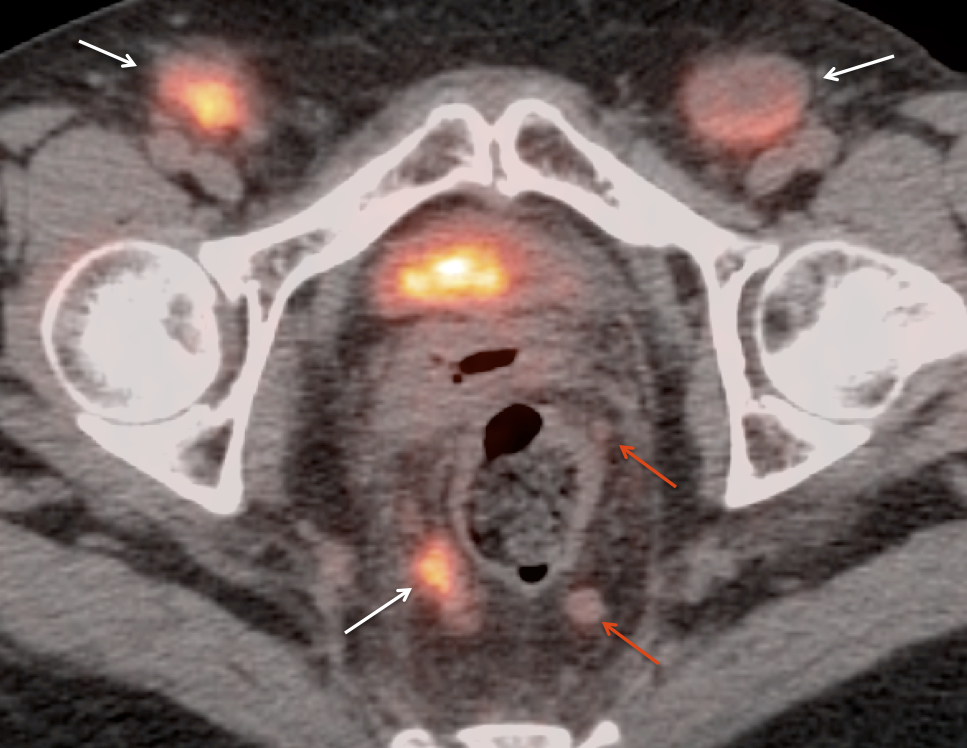

Metastases:

The most common sites of metastatic disease include the lymph nodes (regional & distant), liver, lung, peritoneal cavity, bones, brain and adrenal glands.

• Nodes under 8.0 mm may be non-avid only because they are beneath the resolution of PET (metastatic nodal assessment is discussed in detail, here).

• If < 8.0 mm, even mild uptake in a regional node is “highly suspicious”.

• If < 8.0 mm, even non-avid regional nodes are worrisome, and are considered “indeterminate”.